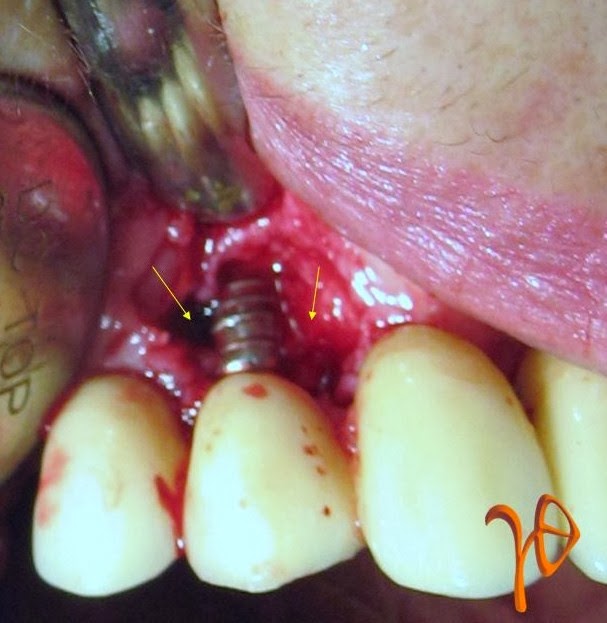

Μια σχετική περίπτωση απεικονίζεται στην παρακάτω φωτογραφία, όπου παρατηρούμε την εξέλιξη της νόσου στο οδοντικό εμφύτευμα #14 που στηρίζει πρόβολο #15 σε συγκολλούμενη ακίνητη προσθετική εργασία. Το μόνο σύμπτωμα του ασθενή ήταν η αίσθηση πόνου κατά την ψηλάφηση της παρειακής επιφάνειας του βλεννογόνου αντίστοιχα με το εμφύτευμα. Η κλινική εξέταση έδειξε παρειακό αιμορραγικό θύλακα βάθους 7mm και άπω υπερώιο βάθους 6mm. Ακτινογραφικά υπήρχε γωνιώδης οστεολυσία κυρίως άπω, αλλά και εγγύς του εμφυτεύματος.

Εικόνα: (α) Η περιοχή κατά την αρχική φόρτιση, (β) Μετά από 5 χρόνια με οστεολυσία (βέλη), (γ) Χειρουργική προσπέλαση που δείχνει το μέγεθος της οστικής απώλειας(βέλη)>/

Η χειρουργική αποκάλυψη της βλάβης επιβεβαίωσε τα κλινικά και ακτινολογικά ευρήματα. Η μεγαλύτερη οστική απώλεια εντοπιζόταν άπω του εμφυτεύματος. Η περιοχή καθαρίστηκε από τους μαλακούς ιστούς, εκπλύθηκε με χλωρεξιδίνη και φυσιολογικό ορό και συμπληρώθηκε με αλλοπλαστικό υλικό και απορροφήσιμη μεμβράνη.